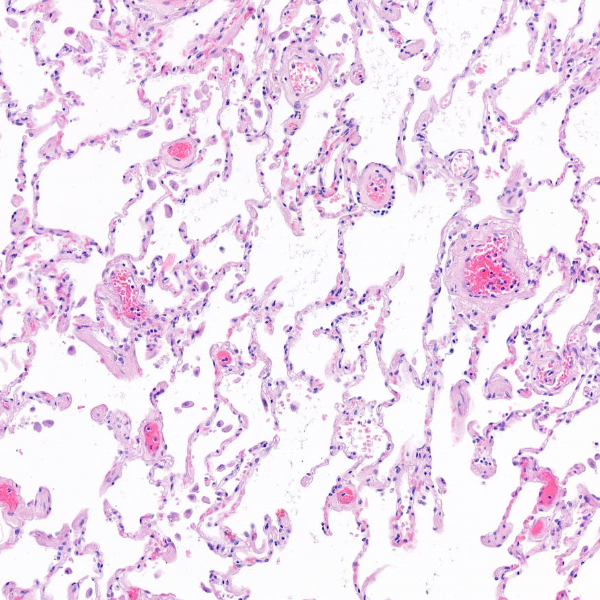

Gesundes Lungengewebe: Mikroskopische Aufnahme einer gesunden Lunge. Die weissen Bereiche sind Lufträume, dazwischen liegen feine Gewebestrukturen, in denen der Gasaustausch stattfindet.